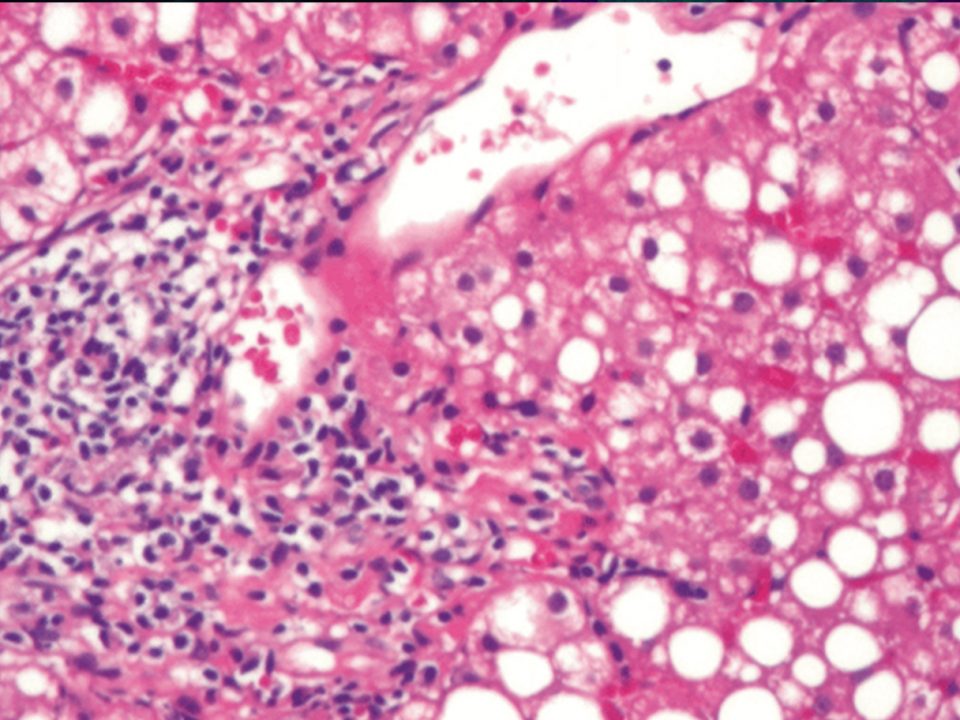

As recognition of fatty liver disease and non-alcoholic steatohepatitis (NASH) as a true global health crisis rises the need to curate and emergency treat the disease in a timely fashion grows as well.

People who have liver disease are 28% more susceptible to viruses and have a greater risk of bacterial infections. Liver diseases lead to a decrease in libido and changes in the condition of the skin and its appendages [10, 11]. Following the epidemic of obesity and type 2 diabetes, non-alcoholic fatty liver disease (NAFLD) is becoming the most frequent liver disease in Western countries. Non-alcoholic steatohepatitis (NASH) is an inflammatory condition caused by fat accumulation in the liver, which presents a serious health concern issue throughout the world, reaching an estimated 5 % prevalence in industrialized countries. It is assumed that NASH originates from a more frequently observed NAFLD characterized by steatosis hepatitis and gamma-glutamyl transferase (GGT) elevation with an estimated prevalence of 25 % in Western and developing countries [12,13,14] .

Progression of liver disease to cirrhosis and HCC is generally limited to the subgroup of patients who developed non-alcoholic steatohepatitis (NASH), a condition characterized by active inflammation and fibrosis [13, 23].

Increased inflammation accompanied by the elevation of transaminases (alanine aminotransferase [ALT] > aspartate aminotransferase [AST]) promotes the progression of NASH to fibrosis and, eventually (in > 20 years) to cirrhosis with a potential to develop into hepatocellular carcinoma, which occasionally can occur without cirrhosis . The pathogenesis of NASH is unknown, although the following predisposing factors are considered: obesity, high-calorie/highfat diet, diabetes, hypercholesterolemia, and certain drugs [30]. However, these risk factors may be completely absent, indicating a possible impact of genetic background; thus, mutations in the patatin-like phospholipase domaincontaining-3 (PNPLA3) gene were shown to influence the severity of NAFLD [5]. As NAFLD pathogenesis is not completely understood, effective therapeutic approaches are not yet available. Symptomatic normalization of increased body weight, low-calorie/low fat-diet, lowering of elevated cholesterol levels, optimized therapy for diabetes mellitus, and avoidance of harmful medications are often not completely successful. Nevertheless, these measures should be taken to reduce the risk of hepatic steatosis and inflammation.

There are two main pathways of liver cell death is apoptosis and necrosis.